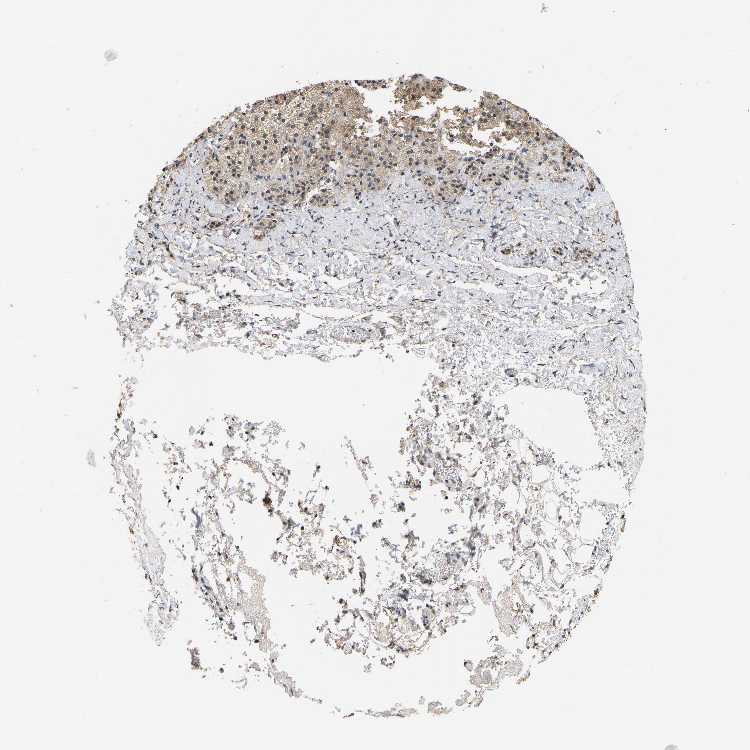

ADRENAL GLAND - Antibody stainingi

Antibody staining in the annotated cell types in the current human tissue is reported as not detected, low, medium, or high, based on conventional immunohistochemistry profiling in selected tissues. This score is based on the combination of the staining intensity and fraction of stained cells.

Each image is clickable and will lead to virtual microscopy that enables deeper exploration of all samples and also displays staining intensity scores, fraction scores and subcellular localization as well as patient and tissue information for each sample.

Antibody HPA019098Antibody HPA020057

Glandular cells LowMedium